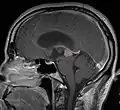

ورم الغدة الصنوبرية

ورم الغدة الصنوبرية Pinealoma هو ورم حميد عادة في الغدة الصنوبرية. تنتج الغدة الصنوبرية هرمون الميلاتونين الذي يلعب دوراً في تنظيم إيقاع الحياة اليومي. وقد يُعطّلُ ورمُ الغدة الصنوبرية إنتاجَ هذا الهرمون، و يسبب الأرق.[2]

التشخيص

من بين الأنواع المختلفة لأورام الغدة الصنوبرية، يبرز النوع الأكثر تفضيلاً عند التشخيص و هو ورم الخلية الصنوبرية.[7]